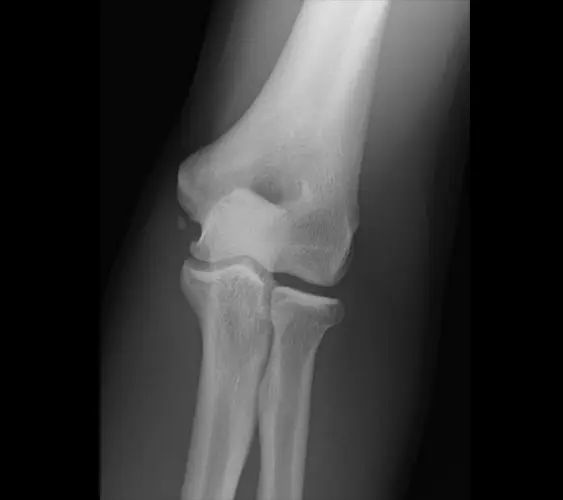

x-ray of ossification within UCL

X-ray demonstrating an ossification within the UCL from chronic use.